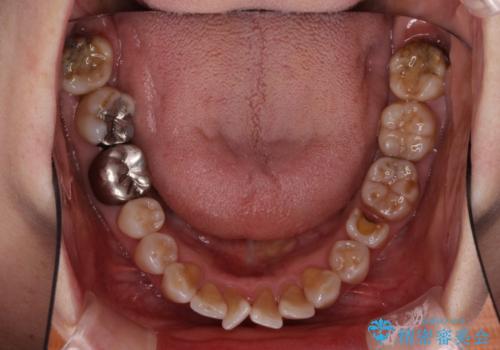

- 口元の突出感と歯の色を気にして来院された患者様です。

口元を引っ込めるために上下左右第一小臼歯4本を抜歯し、ワイヤー矯正を行うこととしました。

歯の色はホワイトニングかセラミッククラウンで対応することとしましたが、ブラックトライアングルが目立つことが予想されたため、目立つ範囲をオールセラミッククラウンで補綴することとしました。